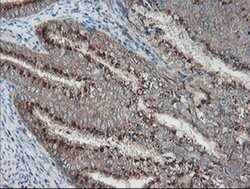

ACBD3 Monoclonal Antibody for Western Blot, IHC (P), Flow

| Flow Cytometry, Immunohistochemistry (Paraffin), Western Blot | |